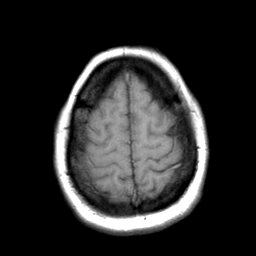

Cerebral hemorrhage, MR Study mr-t1 -- Slice #20

[Home][Help][Clinical] Slice 20